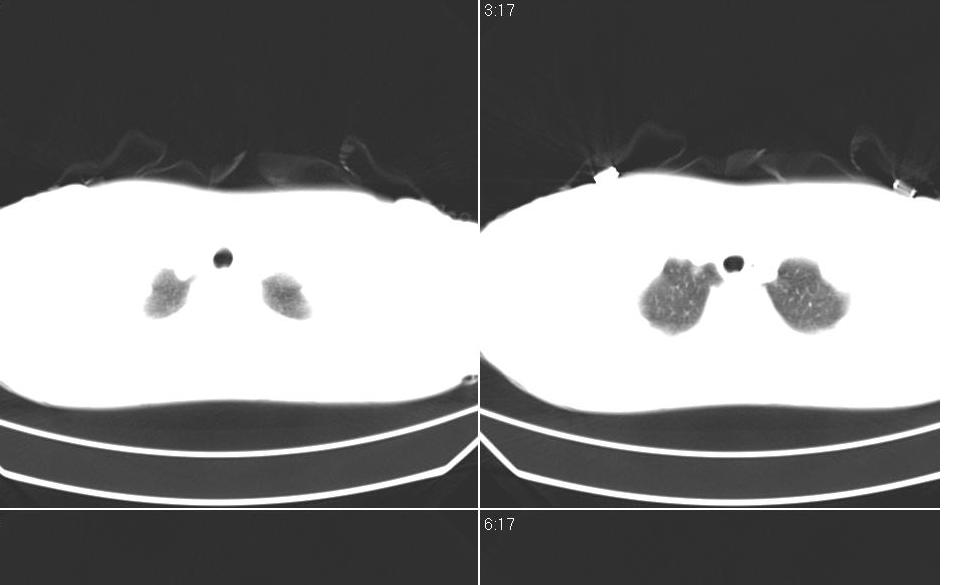

女 40岁,胸片体检发现右肺肿块,无任何症状。

下叶背段多发性小腺泡结节,考虑结核。

考虑侵润性结核

考虑右肺下叶背段继发性肺结核。